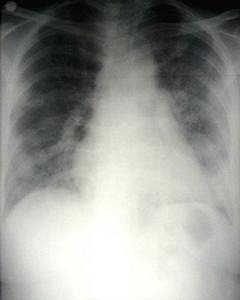

吸入性肺炎胸部X線示於吸入後1~2小時即能見到兩肺散在不規則片狀邊緣模糊陰影,肺內病變分布與吸收時體位有關,常見於中下肺野,右肺為多見。發生肺水腫,則兩肺出現的片狀、雲絮狀陰影融合成大片狀,從兩肺門向外擴散,以兩肺中內帶為明顯,與心源性急性肺水腫的X線表現相似,但心臟大小和外形正常,無肺靜脈高壓徵象。